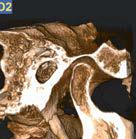

L’innovazione e la sicurezza sono due dei valori perseguiti dallo Studio Braconi a Terni, un punto di riferimento nell’ambito della radiologia 3D ortopedica grazie alla presenza del macchinario Newton 5G XL: si tratta dell’unico apparecchio nel Centro Italia che permette di eseguire una perfetta diagnostica per immagini in ortopedia e per la cervicale, oltre per le piccole articolazioni come seni paranasali, orecchie, colonna cervicale, gomito, polso, mano, ginocchio, caviglia e piede.

Nell’ambito della radiologia 3D ortopedica, il centro diagnostico utilizza il nuovissimo macchinario NewTom 5G XL, in grado di individuare con la massima precisione la presenza di fratture o lussazioni delle articolazioni, controllare la corretta guarigione di una frattura, valutare una lesione o una ferita causata da infezione, artrite o crescita anormale dell’osso.

Il tutto mediante una semplice e veloce scansione, grazie alla quale si otterranno diverse immagini in 3D ad altissima risoluzione e, per ottenere immagini ancora più nitide mediante un bassissimo dosaggio di radiazioni, gli esperti si avvalgono dell’innovazione racchiusa nella tecnologia Cone Beam.

Se con la radiologia tradizionale era necessario eseguire scansioni multiple, la novità introdotta dal macchinario NewTom 5G XL risiede nella capacità di fornire immagini ad alta risoluzione in un’unica scansione, mostrando nitidamente i dettagli delle articolazioni degli arti superiori e inferiori. Inoltre, a differenza della tecnologia 2D, la radiologia 3D ortopedica permette di individuare immediatamente alcune patologie come quella del metatarso, la quale richiede un allineamento visivo dedicato o una diagnosi delle micro fratture ossee.